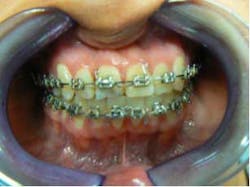

Month 0-3 I like to start all my orthodontic cases off with a light round nickel titanium wire such as an 014N or 012N. While in this wire, I used some elastomeric chain to help align and rotate the teeth.Month 4-10 I continued to level the teeth and begin to reposition brackets on a 18X25 heat-activated NiTi wire based on a panoramic X-ray that I like to take to help me with root positioning.Month 11-16 Progress to a stainless steel 19x25 wire for more tooth torque and better bracket engagement.Month 16-18 Finishing on a 018SS. I don’t have much wire-bending skills, so I mostly move brackets and am capable of only some simple step bends.